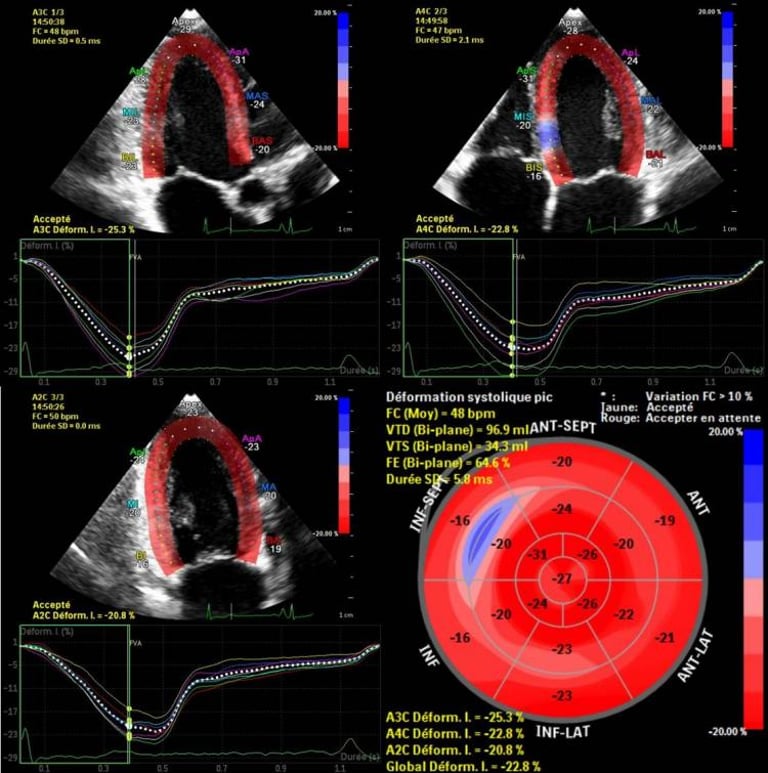

Échographie cardiaque

Évaluation de la structure, des valves et de la fonction du cœur en temps réel.